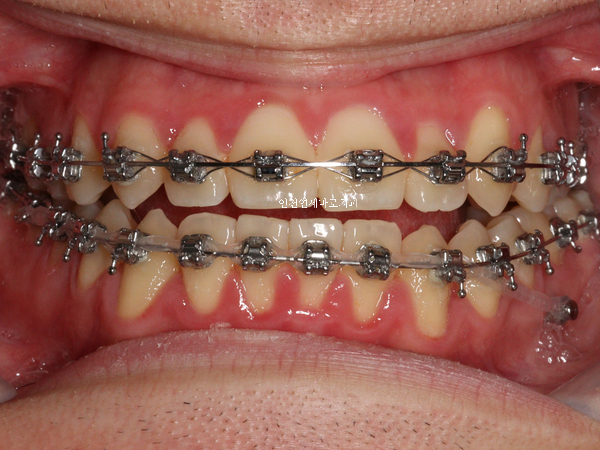

가장 기본이 되는 치료이니만큼 당연히 인비절라인보다 오래치료했고, 저희병원에도 인비절라인보다 더 많은 환자분들이 철사교정을 받고 있답니다.

하지만 대부분의 성인 환자분은 환자분의 의지에 의해 ‘인비절라인’과 장치’철사교정’ 을 선택하여 진행하게 됩니다.

철사교정은 교정의 기초이며 가장 기본이 되는 치료입니다. 철사교정을 못하는 우리나라 교정과 의사는 없으며, 인비절라인보다 오래 치료해온 방법입니다.

연세바로치과에서는 인비절라인보다 철사교정을 받는 환자분들이 더 많습니다. 철사교정이 가장 기본이 되는 치료이며, 인비절라인보다 오래 치료해왔습니다.

- 철사교정(브라켓 교정)을 더 많이 하는 교정과 전문의